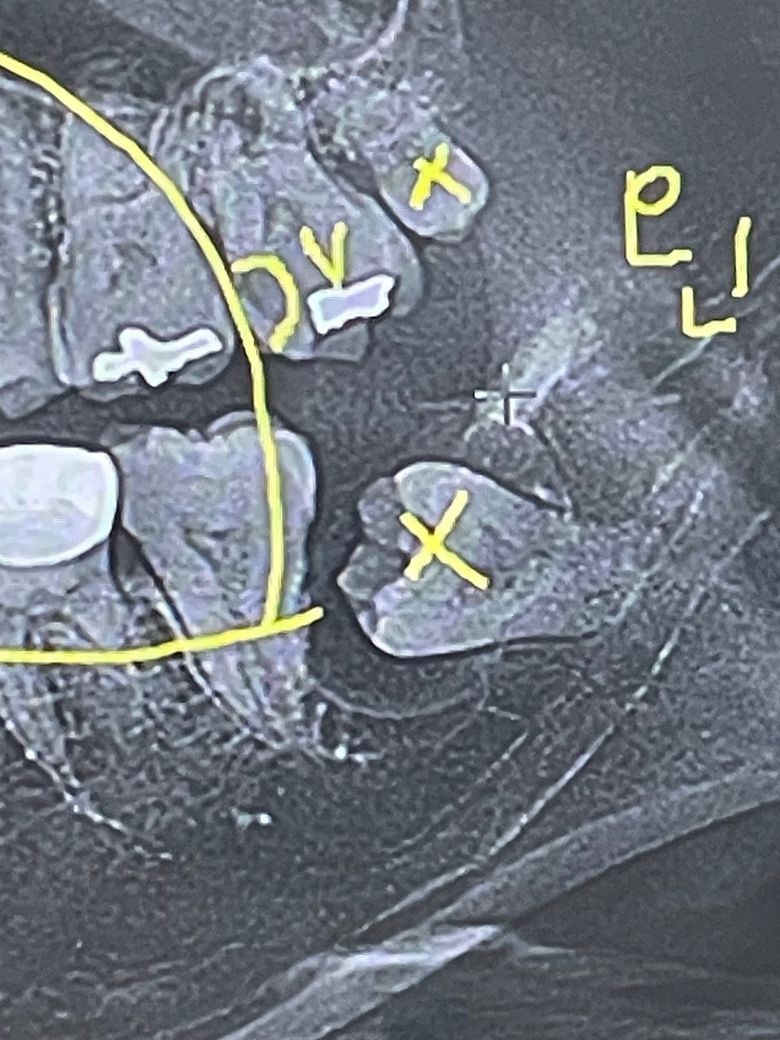

사랑니 발치했는데 주변에 물혹같은게 있다고 했었고 발치전에 심한 악취+고름같은게 나와서 염증 가라앉히고 발치한다고 약3일치 먹고 발치했는데 염증이 그대로라면서 그냥 발치했어요

사진상으로 보면 사랑니 주변에 낭종이 잇엇던거 같습니다. 잇몸이 치유되는데 시간이 꽤 걸릴것같습니다.